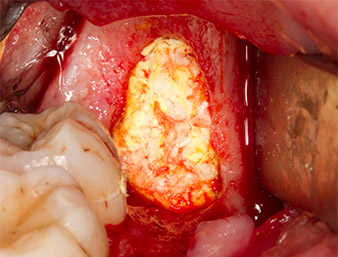

Subsequently, the autogenous bone tissue (Fig. 13) was placed into the alveole and the surrounding bone defect (Fig. 14). Collagen fleece covered the bone chips up to bone level as protection for the exposed nerve (Fig. 15). Sutures using vicryl thread, USP 4.0, were used to close the opened up soft tissue (Fig. 16). An Ibuprofen preparation (Seractil 400 mg, 3x1) and an antibiotic consisting of amoxicillin and clavulanic acid (Augmentin 1 g, 2x1) were prescribed postoperatively.